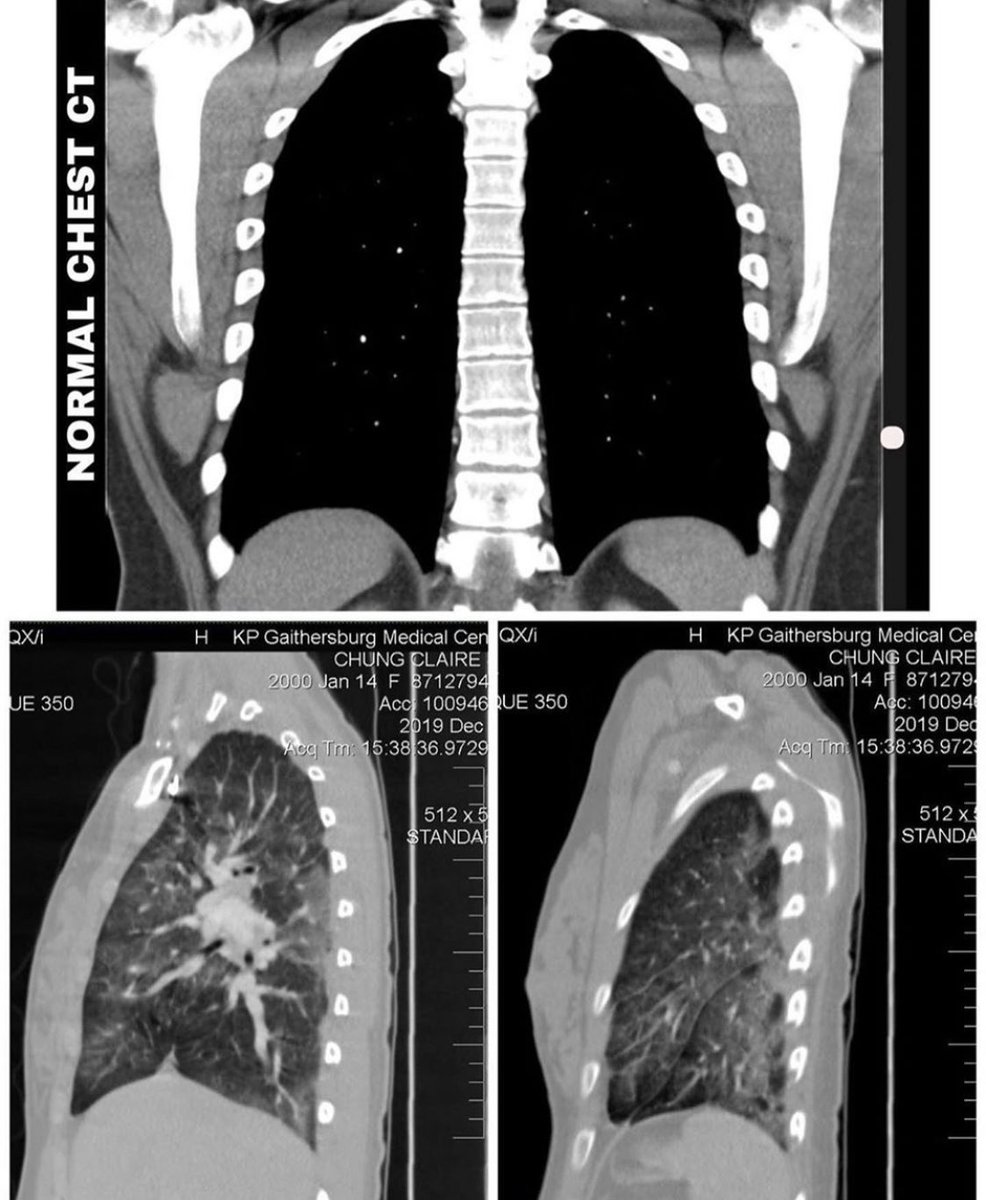

بينت الأشعة المقطعية تزايد في منطقة "الالتهاب" لتشمل الرئتين بالكامل، ولذلك تم تنويمها في العناية المركزة تحت العزل التنفسي والبدء في مضادات حيوية عن طريق الوريد

لكن النتيجة بينت تهتك وتحلل في أنسجة الرئتين مما اضطرهم للبدء بأدوية مناعية قوية عن طريق الوريد وتم وضعها على جهاز التنفس للحفاظ على حياتها حتى إشعار آخر!